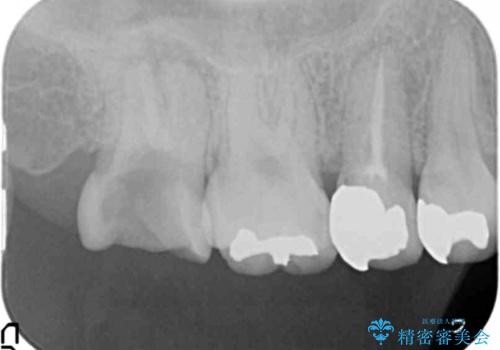

放置した虫歯を外科を行い抜歯を回避

- 放置していた虫歯が欠け、いよいよ怖くなり治療を希望され来院されました。

虫歯は、その進行度によりさまざまな治療法が提案されますが、

エナメル質・象牙質に限局する虫歯 →インレー修復

歯の神経に達する虫歯 →根管治療 クラウン補綴

歯ぐきよりも深い虫歯 →歯周外科による歯周環境の整備

を適宜行うことで良好な結果を得ることができます。

症状に応じて適切な処置を行ったことで、抜歯を回避し良好な結果を得ることができました。